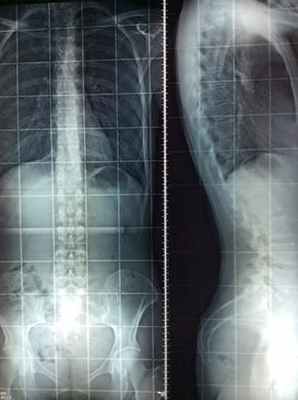

– Случай 17584. Заметное уменьшение искривления позвоночника после лечения по методу Filum System®. Снимок до операции 2014 года и после операции 2015 года.